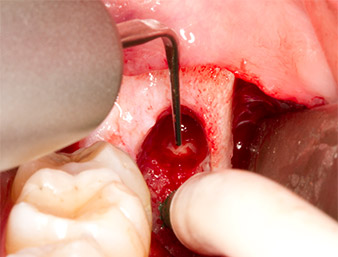

Incision du sulcus

Fig. 3 : L’incision du sulcus démarre au milieu de la dent 36 (LL6), avec extension distale sur le ramus ascendant.

Le tissu recouvrant le reste radiculaire n’est pas entièrement ossifié et est essentiellement constitué de tissu de granulation modifié par l'inflammation (Fig. 4).

Tissu de granulation

Fig. 4 : Deux écarteurs Lagenbeck et un raspatoire exposent la zone d’intervention. On aperçoit le tissu de granulation de la première ostéotomie non totalement cicatrisée.